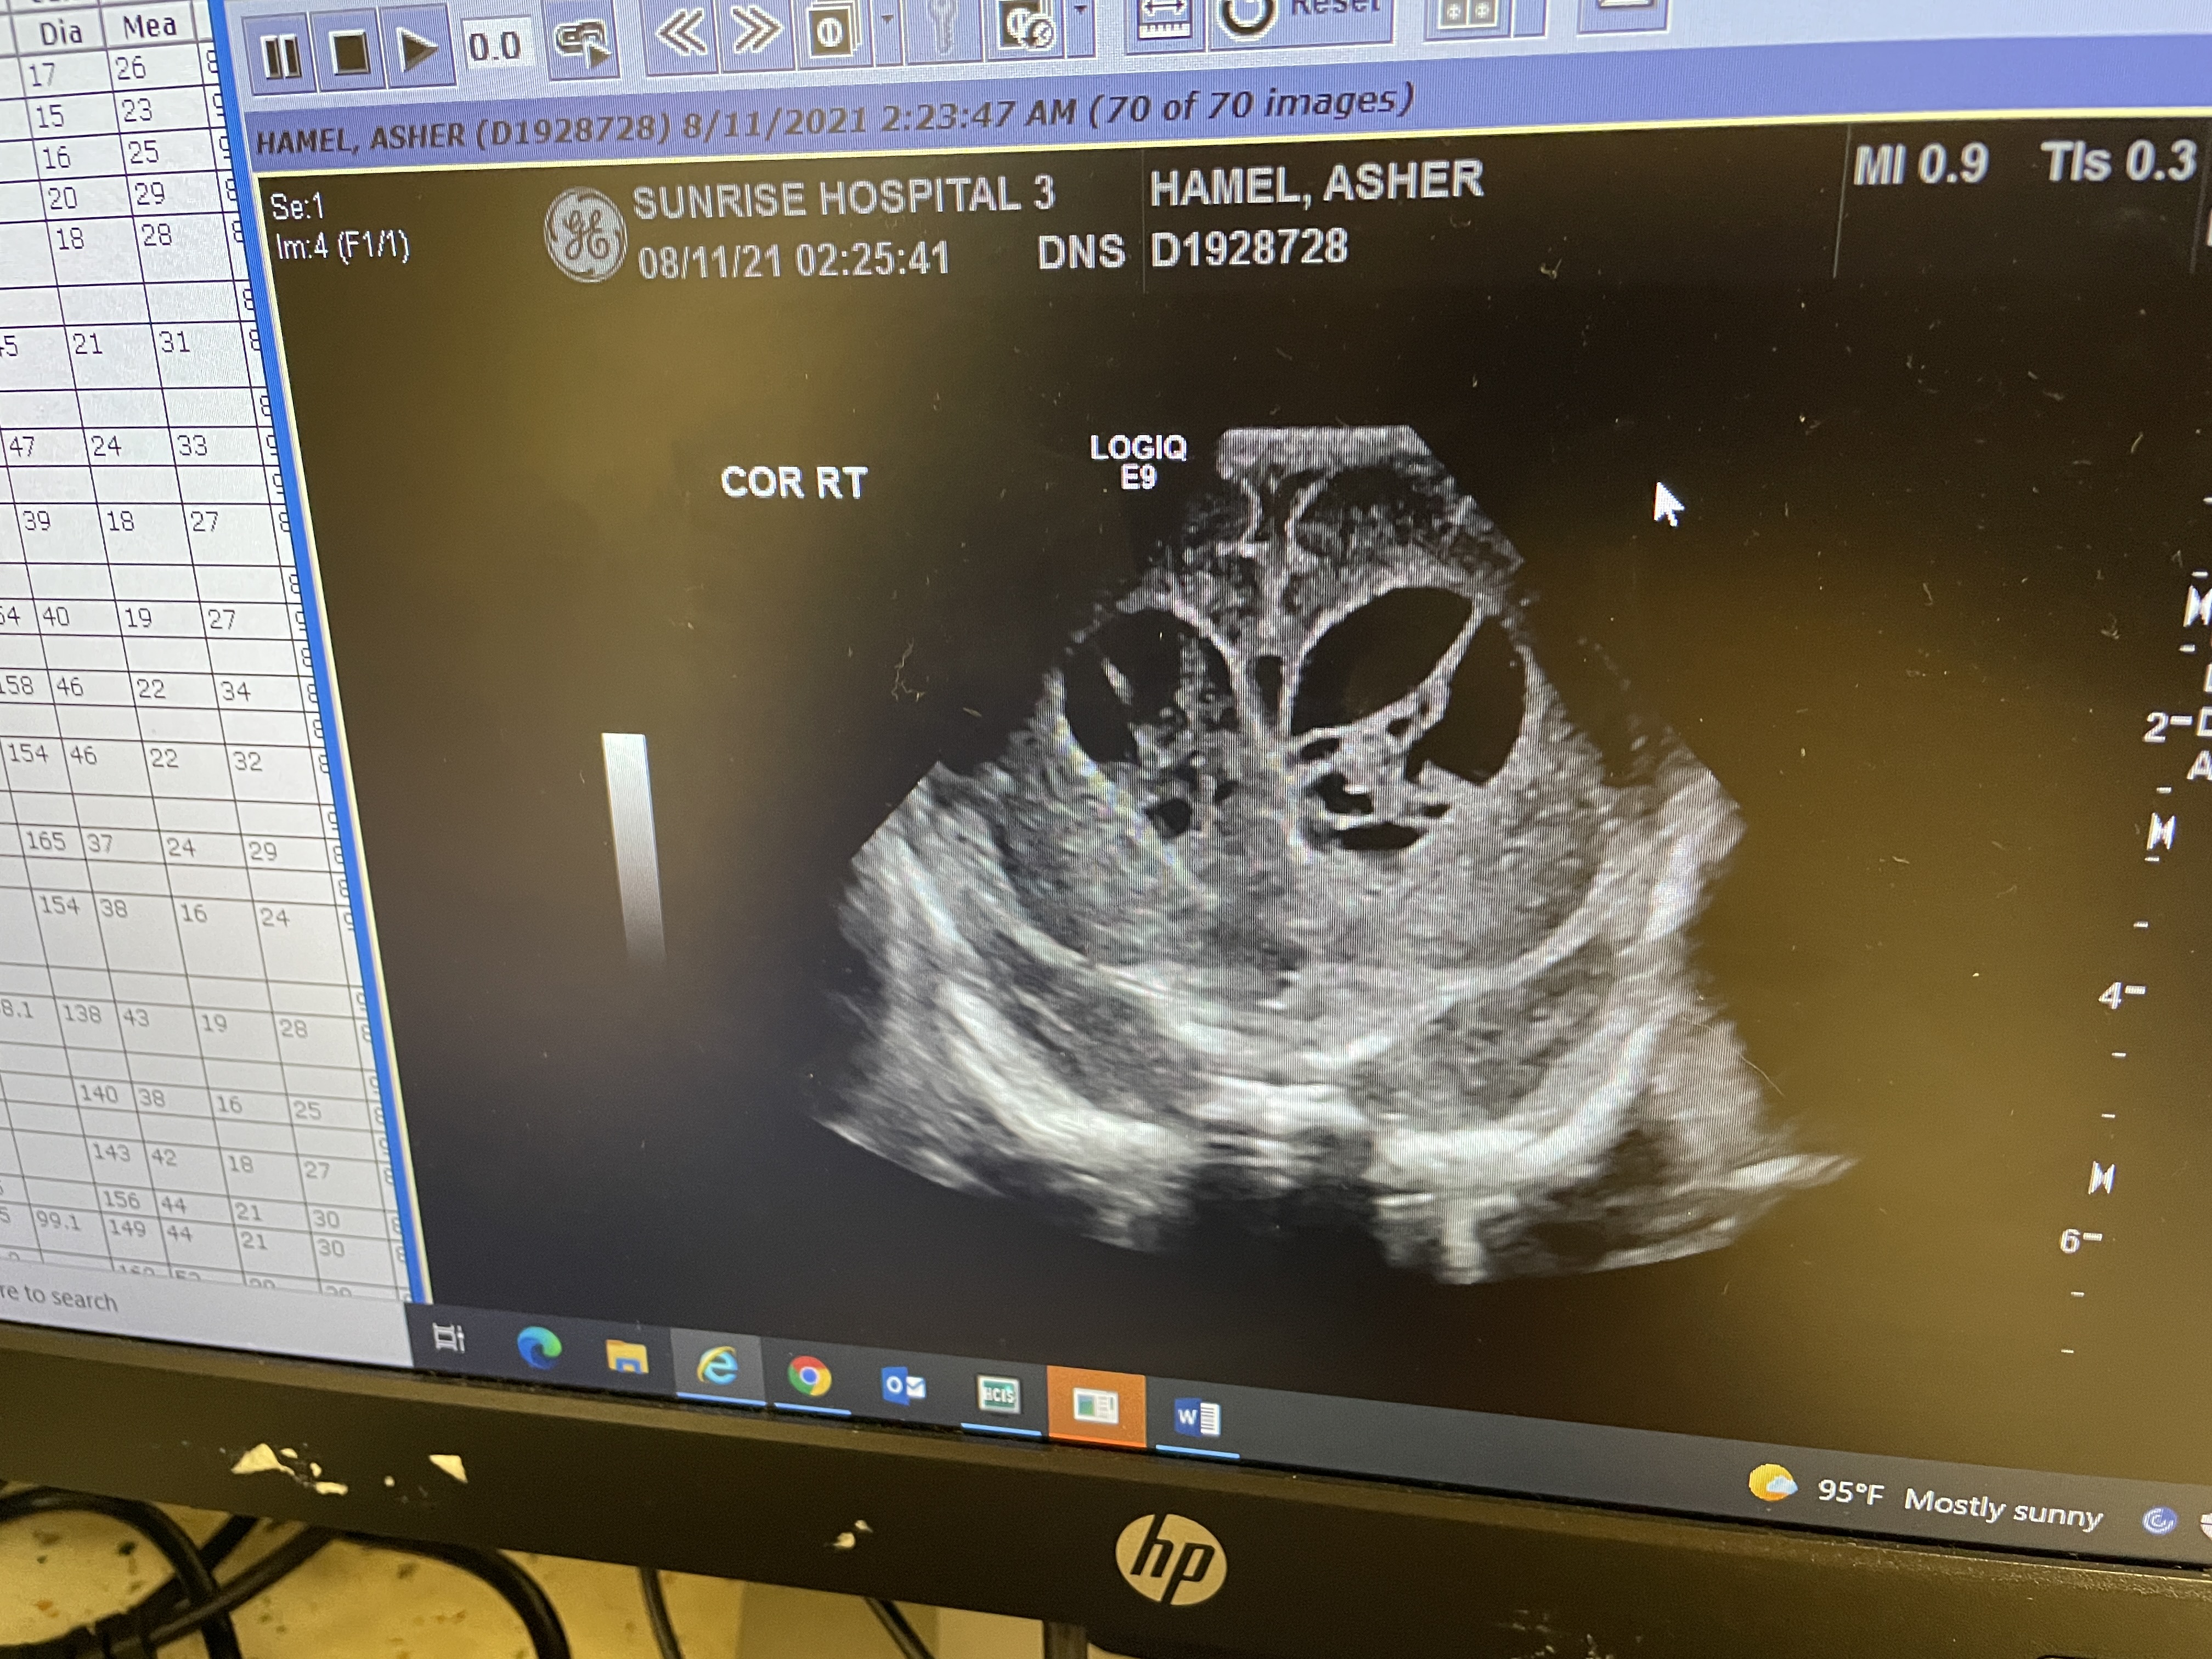

Ultrasound Images

The images show Asherās cerebral ventricles having some sort of āwebbingā inside them. His ultrasound from the week prior didnāt look like this at all. The Dr isnāt sure if itās new blood, old blood moving, or anything elseā¦

Good News: the size of his head is still within normal range. Theyāre not concerned about any abnormal growth at allā¦

The result from yesterday afternoons ultrasound are in…

They either show new bleeding (very unusual) or the way the old blood looks has changed. Dr Lipsky said it’s hard to tell and is waiting on neurosurgeon to review the images…

She did say that it looks as if there’s septation in his ventricle/s (some stringy stuff) but isn’t sure. We’ll be getting a clearer definition of septaion once we get to the hospital today. She did mention “something has definitely changed in his brain and that it could be an abscess as well.”